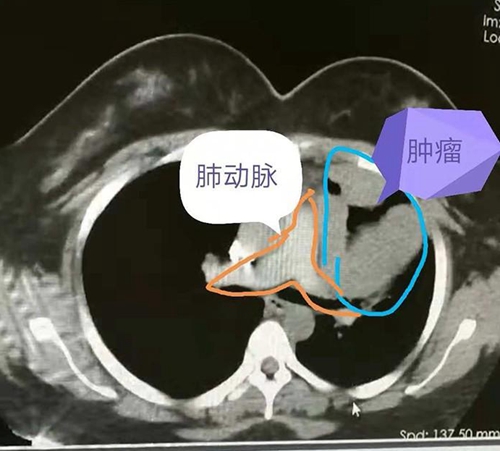

可是,女孩没有想到的是,肿瘤的生长超出预期,最近两周突然出现睁不开眼的情况。再次就医,医生告诉她,这应该是胸腺瘤生长造成的重症肌无力。再次检查,发现肿瘤较8月份明显长大, 同时发现肿瘤压迫了心脏大血管和肺组织。

手术中发现肿瘤侵犯了肺动脉外膜,对肺也有侵犯,经过2个多小时的仔细剥离,终于完整切除了肿瘤,同时,还切除了部分心包和受侵犯的肺组织。